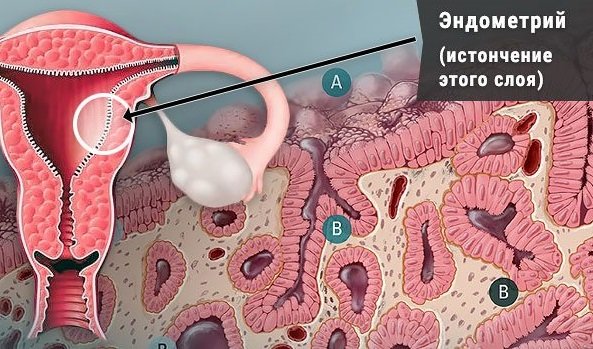

Медицинская диагностика: Гиперплазия эндометрия на УЗИ